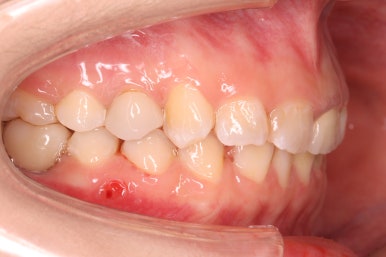

측면에서 본 모습입니다.

자리가 점점 넓어지는 것이 보입니다.

키다리아저씨치과에서는 부산부분교정을 통해 어금니가 충분히 뒤로 이동을 하면서 공간이 확보 되었다고 생각되면 임플란트 식립이 완료가 될 때까지 유지를 해줍니다. 유지가 원활히 되지 않으면 임플란트가 최종 완성되는 몇 개월간 다시 쓰러질 수 있거나 위치가 변할 수 있기 때문이죠.

화살표를 보시면 교정치료를 하지 않은 윗니들을 변화가 생길 것을 미리 염려해 철사를 붙여두었습니다. 임플란트 식립이 필요로 한 옆 치아에도 붙이고 미니스크류를 연결을 시켜 놓는 등 적극적으로 힘을 주는 과정이 아닌 현재를 유지하기 위한 장치입니다.